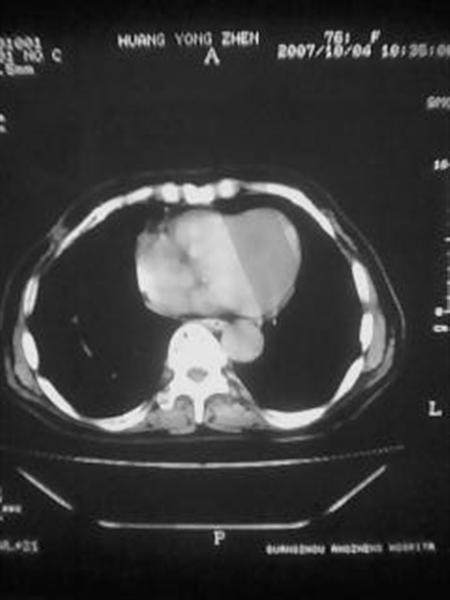

标题: CT10080:F76Y,各位老师发表高见!!! [打印本页]

标题: CT10080:F76Y,各位老师发表高见!!!

右下肺周围型肺癌伴双肺右侧叶间 胸膜及右肺门淋巴结转移

考虑:肺癌伴肺、胸膜 纵隔淋巴结转移可能性大!